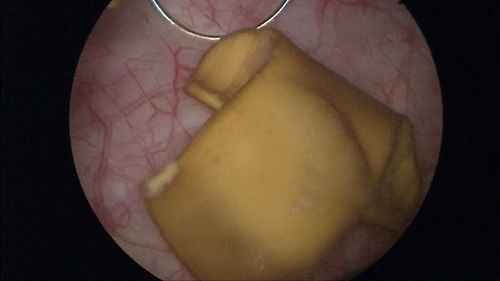

影像学检查:如经直肠或腹部超声、CT或磁共振成像(MRI),可以精确测量前列腺的三维尺寸并计算其体积。

直肠指检(DRE):医生通过手指触诊,可以直观感受前列腺的大小、质地、表面光滑度及有无结节,初步判断其健康状况。